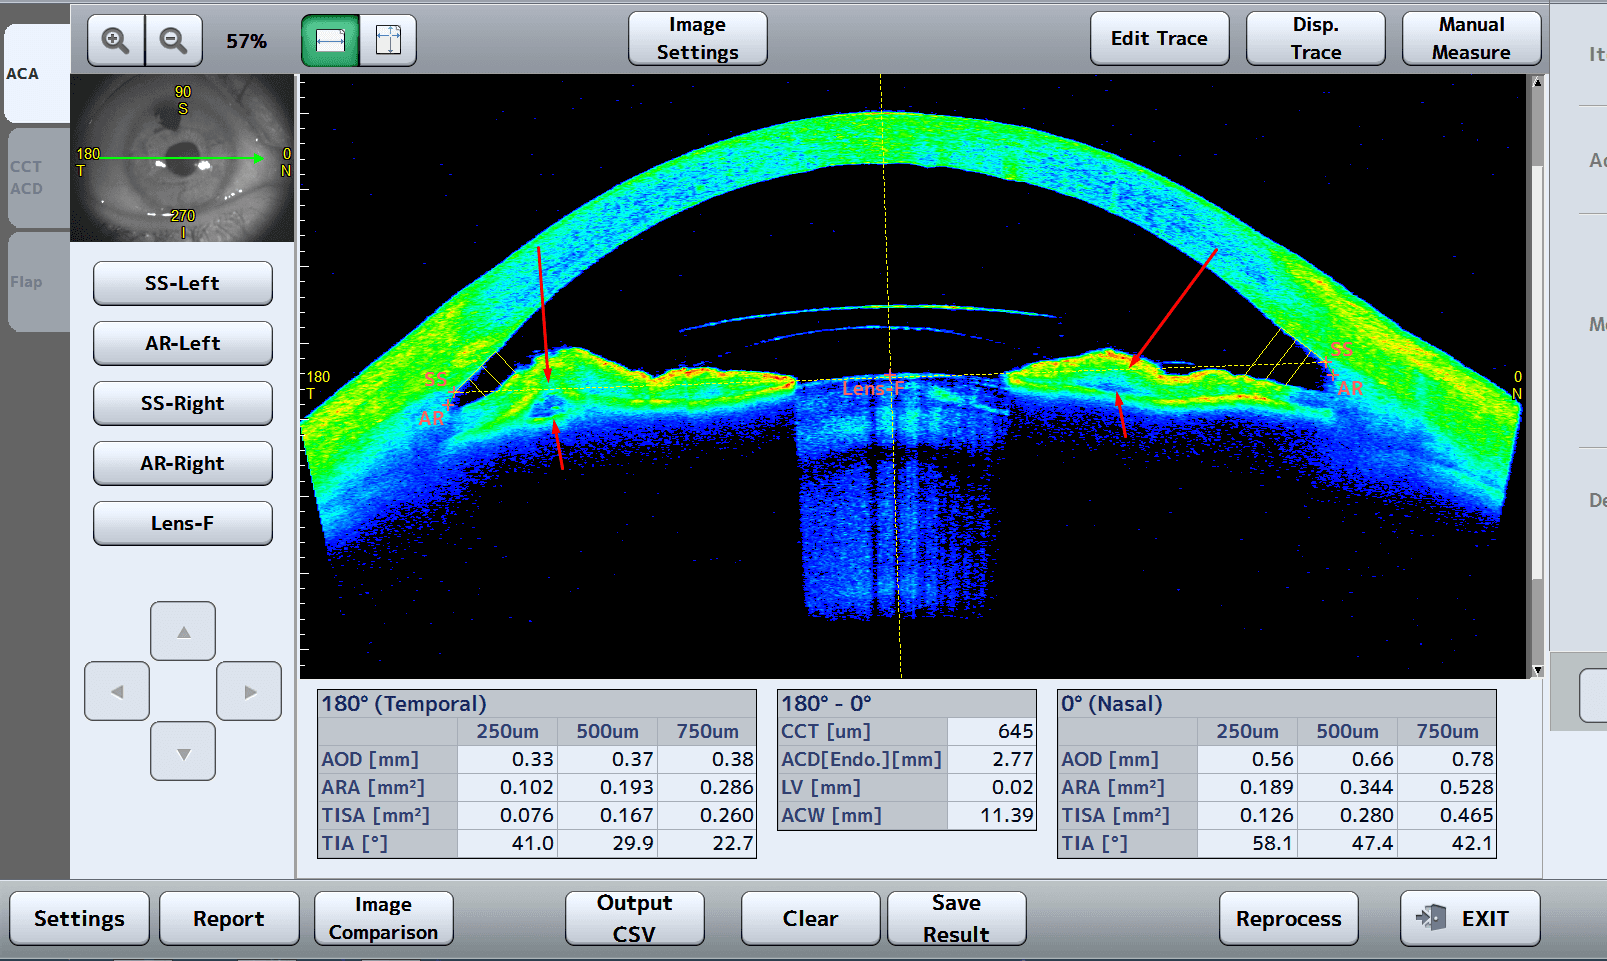

360° anterior chamber angle measurements with automatic scleral spur detection

STAR Analysis - Glaucoma Application: Automatically measures the anterior chamber angles all around the anterior segment with automatic scleral spur detection, providing specific parameters needed to detect and treat glaucoma

Glaucoma angle analysis (360°)